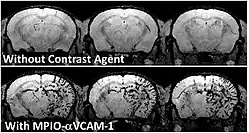

- des marqueurs, sondes ou traceurs, de natures diverses (colorants, produit de contraste, marqueur radioactifs ou opaques au rayons X, émulsion fluorescente telle que la sentidye, des protéines fluorescentes éventuellement produites in situ par l'organisme, après qu'il a été génétiquement modifiée (souris de laboratoire par exemple).

Ces produits (injectés ou ingérés ou produits par un organisme génétiquement modifié pour cela) visent un organe, un type de cellule, ou une molécule particulière qui sera ainsi mise en évidence par l'imagerie.

- rendre visibles in vivo certaines macromolécules, des protéines ou de l'ADN ou d'autres molécules d'intérêt (via des marqueurs spécialisés) ;